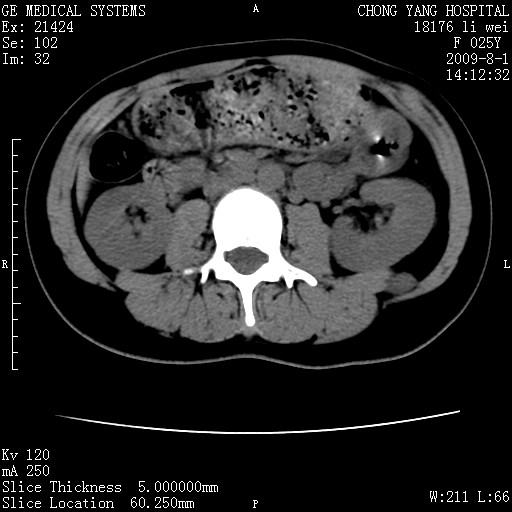

以下是引用pujunzhi在2009-8-1 20:23:00的发言:[br]胸椎旁及背部肌间良性病变,范围广,边界清,沿肌间生长,考虑淋巴管瘤、血管瘤,建议增强扫描。

以下是引用拾荒者在2009-12-30 21:45:00的发言:[br]ct21383:神经纤维瘤病( nf) [br] [br] 神经纤维瘤病。四肢都有,影响美观,四肢上的手术了。[br] [br] [br]谢谢!